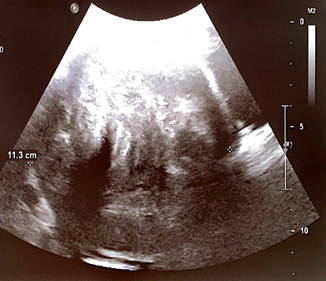

A 40 years old pregnant patient with two vaginal term deliveries in the past presented for delivery in 37 week of gestation. The physical examination revealed a height of fundus uteri corresponding to the term of amenorrhea, strongly displaced to the left froma myoma cervix without dilatation and presenting part of the fetus, which was not reached. Ultrasound examination revealed eutrophic fetus in breech presentation and the presence of a large myoma in the isthmic part of the uterus with a measured maximum diameter of 11.3cm (Figure 1).

Figure 1 Ultrasound image of the myoma.